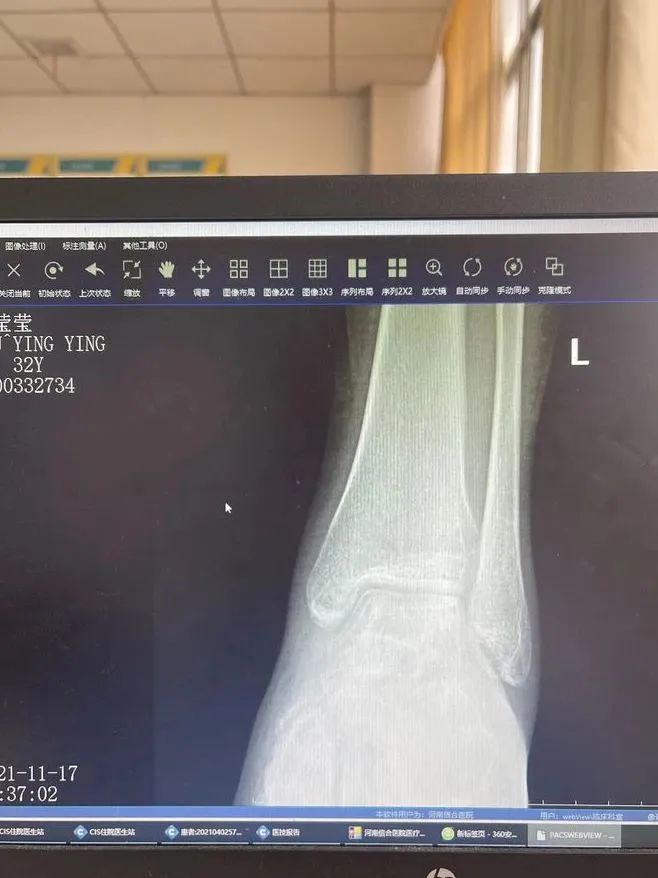

不出所料,在刘女士部分负重恢复一个月后,复查 DR 显示:踝穴宽度满意,距骨无内外移位,胫距关节面间隙正常且无变窄和增宽!这意味着,原本因外伤导致距骨脱离的刘女士,已经摆脱了截肢和残疾的风险,行走功能即将恢复如初!